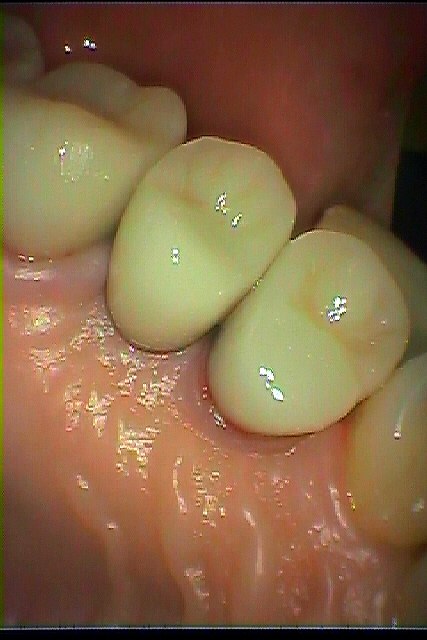

チタンのアバットメント、セラミッククラウンにて上部構造を作成しています。| |広島市安佐南区の歯科医院 チタンのアバットメント、セラミッククラウンにて上部構造を作成しています。 トップ お知らせ・ブログ チタンのアバットメント、セラミッククラウンにて上部構造を作成しています。 チタンのアバットメント、セラミッククラウンにて上部構造を作成しています。 Web診療予約 初めての方へ 選ばれ続ける理由 院内設備について 歯が痛いしみる一般歯科 歯がぐらぐらする歯周病 健康な歯を保ちたい予防歯科 子供の虫歯予防をしたい小児歯科 銀歯をセラミックに審美歯科 白い歯を目指しませんか?ホワイトニング 矯正専門医がいるので安心矯正歯科 抜けた歯を補いたいインプラント・入れ歯 医院案内 スタッフ紹介 メリィハウス歯科クリニックオフィシャルホームページ ラベンダー歯科クリニックオフィシャルホームページ お知らせ・ブログ ホーム 診療科目 一般歯科 歯周病治療 予防治療 小児歯科 審美治療 ホワイトニング 矯正歯科 入れ歯・インプラント マウスピース矯正 初めての方へ 院長・スタッフ 設備紹介 医院案内・アクセス メニューを閉じる